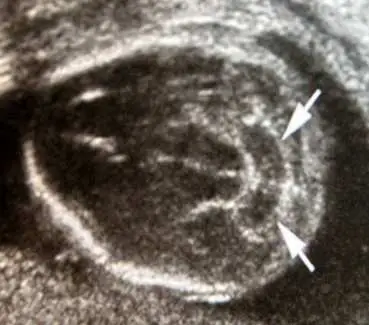

29 歲孕婦,G3P2 ,妊娠 18 週,接受超音波檢查,結果如圖所示,圖中箭頭所指之胎兒異常器官名稱與特徵( sign )為何?

超音波影像呈現胎兒頭部橫切面(transverse axial view),影像中央可見顱骨回聲環。兩支白色箭頭所指位置位於後顱窩(posterior fossa),指向一個弧形彎曲、形似香蕉的低回聲構造,即為向下移位並包繞腦幹(brainstem)的小腦(cerebellum)。

正常小腦在橫切面呈啞鈴形(dumbbell shape)或圓形,但本影像中小腦兩側半球向前彎曲緊貼腦幹,形成所謂的 banana sign(香蕉徵)。此形態改變係因脊椎裂造成腦脊髓液(cerebrospinal fluid, CSF)外漏,使顱內壓降低,腦幹與小腦蚓部(cerebellar vermis)向下疝入頸椎管,即 Arnold-Chiari II 型畸形的病理機轉。後顱窩較正常狹小,cisterna magna 消失,是輔助判讀依據。